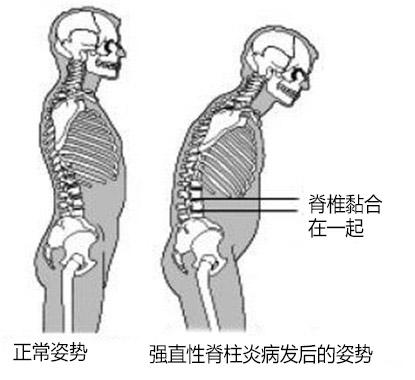

怎样预防强直性脊柱炎的危害?需做好以下三点

说起强直性脊柱炎,很多朋友都只知道这是一种骨科疾病,会导 ...

成都强直专科医院,大家要认真对待强直性脊柱炎的预防工作

面对强直性脊柱炎疾病的发生,强直性脊柱炎病人的生活平衡和和谐 ...

成都强直性脊柱炎医生,你了解强直性脊柱炎的具体预防环节吗

在强直性脊柱炎疾病发生之前,为了避免不必要的伤害,我们一定要 ...